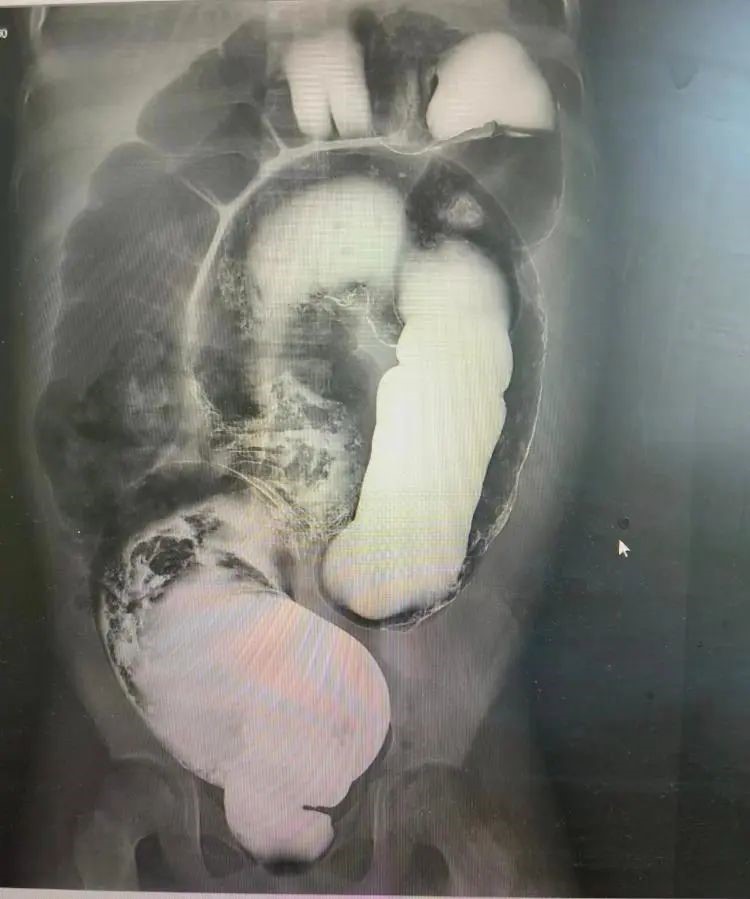

周鹏立即安排他进行相关检查,CT检查报告提示,结肠广泛显著扩张,结合病史符合先天性巨结肠影像表现。患儿的血色素只有3克,只有正常人的四分之一,再拖下去很有可能发生生命危险,周鹏决定抓紧为明明实施手术,然而因为母亲残疾,家庭生活开销只能靠父亲打零工维系,明明父母东拼西凑只交上了200块的住院费,远远不够手术费用。